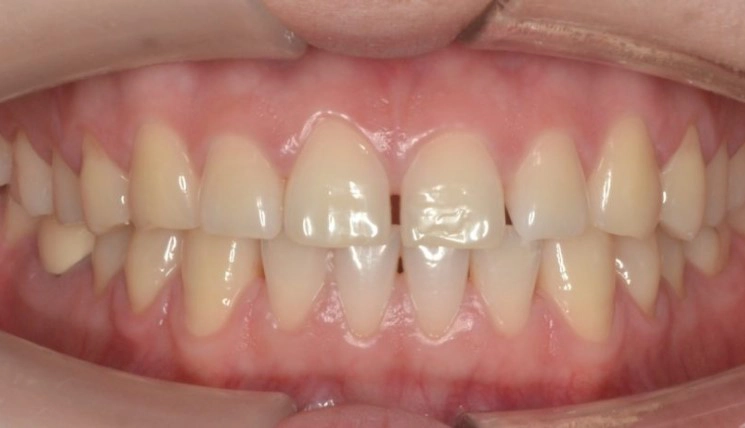

Midline Discrepancy

Midline discrepancy is the condition in which there is a misalignment of the midsagittal line of maxillary and mandibular arches respectively and/or relative to the facial midline.

Patient Information:

Age: 28

Gender: Female

Invisalign Treatment Option: Invisalign Comprehensive

Total Treatment Time:

16 months